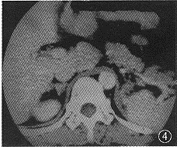

图4 术后5个月增强CT复查。强化后右侧肾上腺区软组织密度影

术后近5个月复查CT(增强扫描)时发现右侧肾上腺区软组织影(考虑转移)(图4)。1个多月后病人头痛,头颅CT检查发现颅内多个球形略高密度影(考虑转移),病人10 d之内死亡。